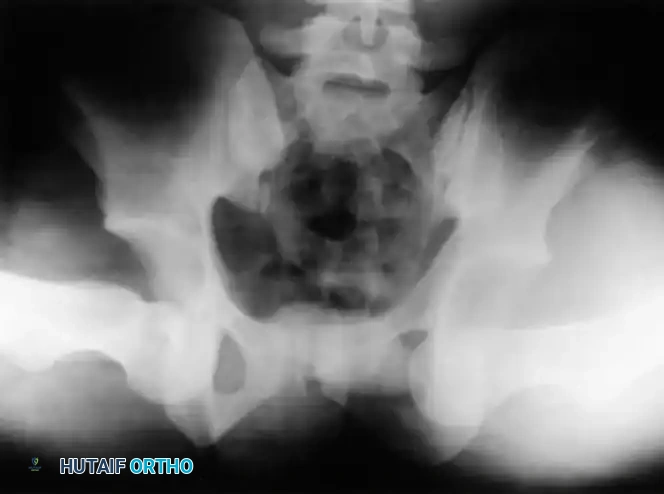

Immediately following closed reduction, a repeat anteroposterior (AP) pelvic radiograph is mandatory to confirm concentric reduction.

Clinical Pearl: Nonconcentric reduction is a subtle but critical finding. It is radiographically identified by a persistent widening of the medial joint space—specifically, the distance between the radiographic teardrop and the femoral head—when compared to the contralateral normal hip.

Fig. 52-45 Widening of the medial joint space after closed reduction indicates a nonconcentric reduction, highly suspicious for entrapped osteocartilaginous fragments or labrum.